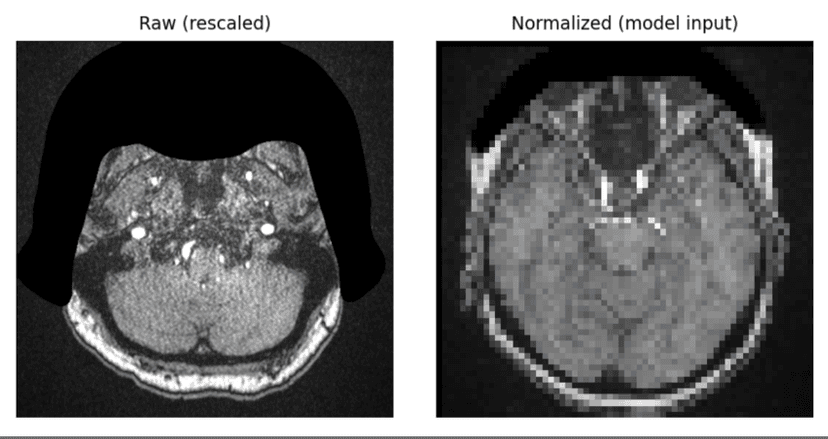

Slice-based CNN pipeline on RSNA Kaggle brain scans using modality-aware preprocessing and depthwise aggregation across slices. Achieved around 0.62 AUC for efficient aneurysm detection and localization.